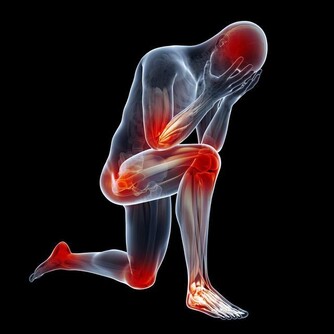

隨著年齡增長,很多人筋骨不如從前了,爬個樓、登個高,很容易就感覺關節痛。

特別是這個季節,天氣轉冷,更是動不動就膝蓋疼。

跟很多中老年人一樣,國醫大師年老時,也遇到了這樣的問題,上下樓梯時,都感到膝蓋疼。

他沒有吃鈣片,也沒有吃止痛藥,而是自創了一套“關節按揉法”,揉了三四個月,就感覺好多了。

具體是怎麼做的呢?首先,坐下來伸直雙腿,將掌心按在髕骨上,從外往裡揉,揉38下,再從裡往外,揉38下。

然後,雙手分別抓住雙腿的髕骨,往上提38下。

接著,屈起雙腿,用手指同時按揉外膝眼、內膝眼,共38下。

“每天早上起床時,坐在床上屈膝揉一次,晚上睡覺前揉一次。堅持兩三個月,對關節健康很有好處。”